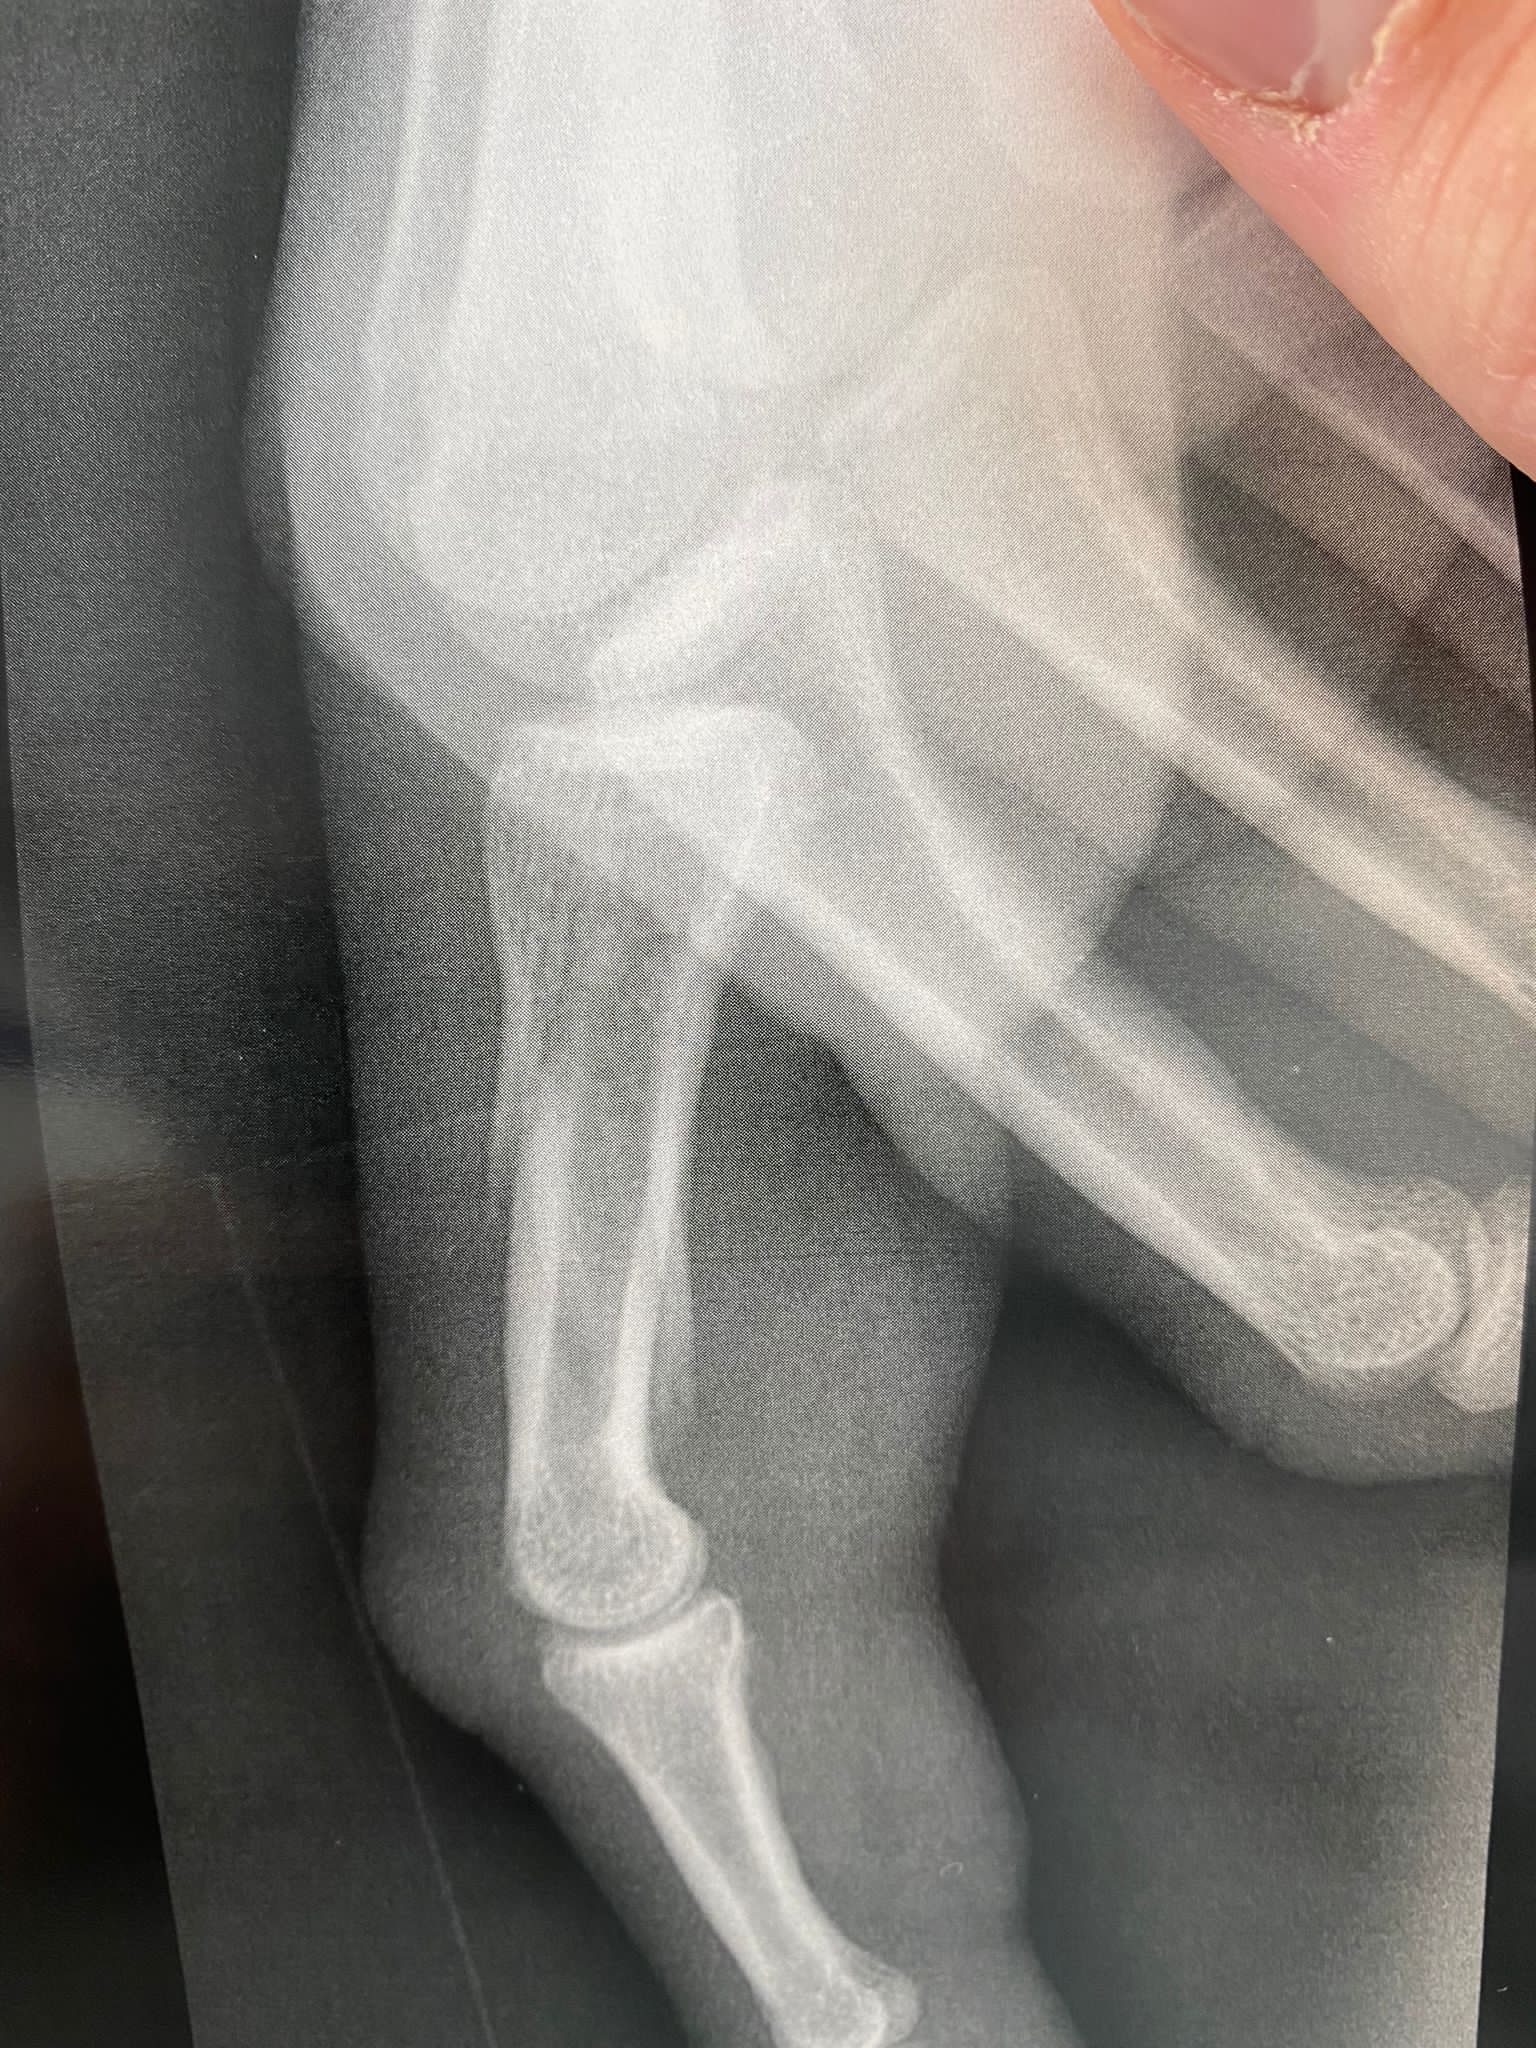

Kapiten košarkaške reprezentacije Bosne i Hercegovine Miralem Halilović doživio je tešku povredu u utakmici francuskog kupa.

Poslije samo četiri minuta igre u kup utakmici između Orelansa i Nanterrea Miralem Halilović je slomio prst. Teška povreda će bh. reprezentativca udaljiti sa parketa prema prvim pognozama najamanje do kraja 2022. godine.

Povreda kapitena Zmajeva je teže prirode, a u foto galeriji koja se nalazi u prilogu možete pogledati trenutni izgled prsta košarkaša Nanterrea.